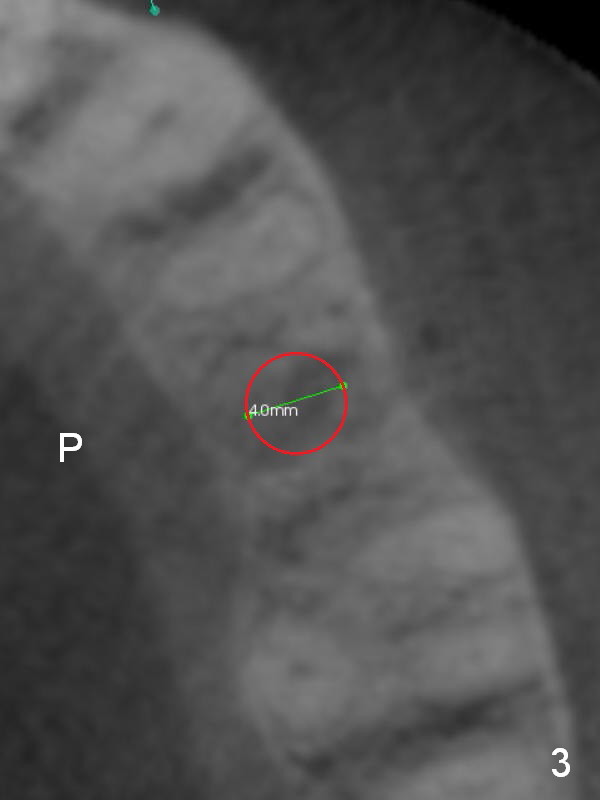

A 74-year-old man has diabetes. Implant osteointegration appears to be slow at #4, while the implant at #28 failed once. He requests implant at #13 (Fig.1). It seems that the bone is wide enough (8 mm, Fig.2 (CT coronal section) (P: palatal)) to hold a 4 mm implant (Fig.3 (axial section)). Since bone density is low at the coronal (100-200 units) and middle (50-100 units) segments (Fig.2), bone condensation will be beneficial. To facilitate wound healing, flapless approach is adopted using 1.6 mm pilot drill (Fig.4), followed by 1.4/2.6 mm bone expander. In fact there is resistance to expansion in the zone 1. Magic expander (3.0 mm) is also tried with difficulty. It appears that bone density is higher than expected. The second portion of Magic Surgical Kit is then used: 3.3 mm Magic Drill for 15 mm (gingival level, followed by Final Drill). A 4x13 mm IBS implant is seated incompletely. The osteotomy is further enlarged by 3.8 mm Magic Drill for 11 mm and deepened with 3 mm drill until 18 mm. Finally the implant is placed at a satisfactory level with insertion torque > 50 Ncm (Fig.5). A 4.5x4(3) mm abutment is placed and periodontal dressing is applied. The patient chooses to return for impression 6 months postop (Fig.6). The abutment changes to a 4x4(4) mm one. The crown is recemented nearly 2 years post cementation, which is related to distal and deep placement of the implant and bruxism (Fig.7).